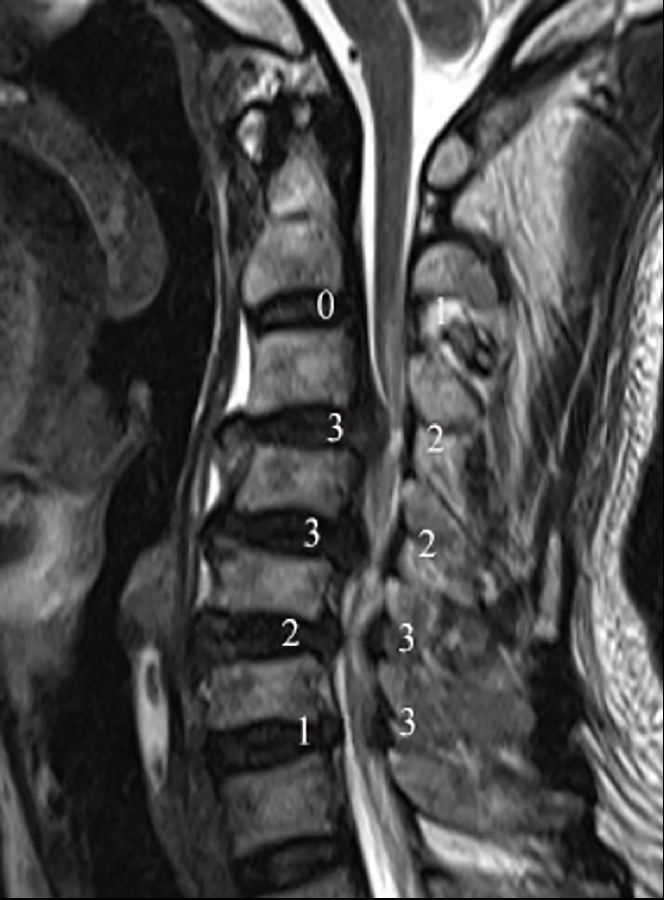

3.1颈椎MRI矢状位脊髓压迫比值

依据Fehlings等报道的方法测量颈椎MRI矢状位脊髓压迫比值(compression ratio of the spinal cord,CRS)。分别测得颈椎MRI矢状位,压迫程度最重节段脊髓直径(dc),上方椎体水平非压迫节段脊髓直径(ds)以及下方椎体水平非压迫节段脊髓直径(di)(图1)。其中选择MRI正中矢状位或旁矢状位测量,依据颈椎间盘压迫位置,分为中央型与旁中央型。CRS具体测量公式如下:

3.2 颈椎间盘突出程度

颈椎间盘突出程度依据颈椎MRI矢状位椎管压迫比值(compression ratio of the cervical spinal canal,CRCS)。椎管压迫比值CRCS与脊髓压迫比值CRS测量方法类似,只是前者测量的是椎管整体压迫程度,后者关注的是脊髓本身压迫程度。分别测得颈椎MRI矢状位压迫程度最重节段椎管直径(Dc),上方椎体水平非压迫节段椎管直径(Ds)以及下方椎体水平非压迫节段椎管直径(Di)(图1)。CRCS具体测量公式如下:

图1.颈椎MRI矢状位脊髓压迫比值和颈椎间盘突出程度的测量方法。颈椎MRI矢状位,压迫程度最重节段脊髓直径(dc),上位椎体水平非压迫节段脊髓直径(ds)以及下位椎体水平非压迫节段脊髓直径(di);压迫程度最重节段椎管直径(Dc),上位椎体水平非压迫节段椎管直径(Ds)以及下位椎体水平非压迫节段椎管直径(Di)

颈椎节段后凸角度测量使用Harrison椎体后切线法,此测量方法相较Cobb角法对颈椎后凸的评估更可靠。本研究中,我们尝试探索退变性颈椎后凸对神经功能的影响,Harrison椎体后切线法更直接评估椎体后缘成角而非椎体上下终板交角对脊髓的影响,可能会提高测量结果与脊髓神经功能损害程度的相关性(图1)。分别测量了在颈椎MRI矢状位像上、颈椎侧位X线、过屈位X线及过伸位X线上的颈椎节段角度。本研究中颈椎前凸角度定为负值,颈椎后凸角度定为正值,以°为标准界定颈椎后凸。